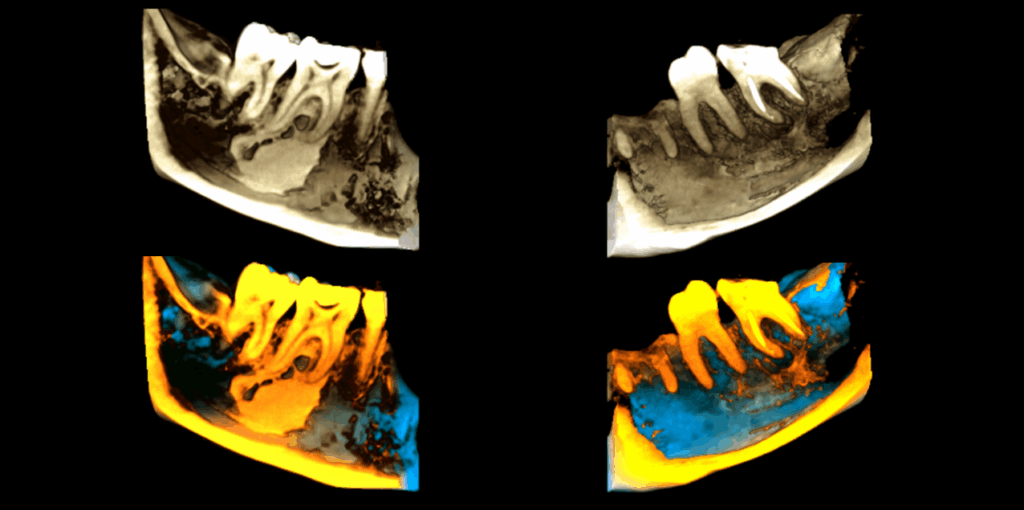

En el estudio complementario mediante tomografía computarizada de haz cónico (TCHC), se observa la obturación subextendida de conductos en la raíz mesial de la pieza 37, se confirma el proceso osteolítico periapical y el aumento de la densidad ósea circundante con extensión hacia el conducto dentario inferior. En la pieza 46 se observa una restauración oclusal hiperdensa con material restaurador isodenso subyacente próximo a cámara pulpar y se corrobora el aumento de la densidad ósea periapical que además se extiende hacia la tabla ósea lingual.

RECONSTRUCCIÓN 3D